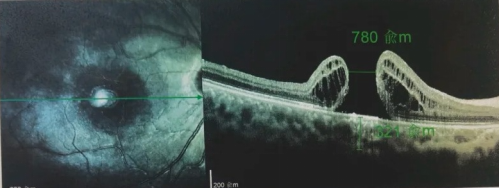

由于自身患有頸椎病,每次術(shù)后長(zhǎng)期的趴睡都讓他痛苦不堪。為了尋求更好的治療,吳爺爺來(lái)到廈門(mén)大學(xué)附屬?gòu)B門(mén)眼科中心,找到了眼外傷及眼底病2科的李海波博士后。此時(shí),吳爺爺右眼的黃斑裂孔已經(jīng)持續(xù)擴(kuò)大到780μm,演變?yōu)殡y治性的大裂孔。

經(jīng)過(guò)完善的術(shù)前檢查和專(zhuān)業(yè)評(píng)估后,李海波博士后決定采用創(chuàng)新的治療方案——SPOT 技術(shù)輔助下遠(yuǎn)周邊移植自體內(nèi)界膜覆蓋,為他進(jìn)行治療,手術(shù)在20分鐘內(nèi)順利完成。

最讓吳爺爺難以置信的是:術(shù)后只需保持平躺24小時(shí)!第二天復(fù)查時(shí),眼底鏡及OCT檢查清晰顯示——那個(gè)折磨了他大半年的大裂孔,竟然閉合了!且吳爺爺?shù)挠已垡暳τ辛嗣黠@的改善,術(shù)后3天已經(jīng)可以看到 0.15。